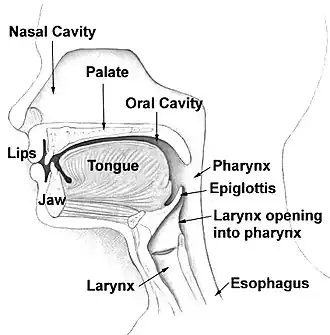

The pharynx (pl.: pharynges) is the part of the throat behind the mouth and nasal cavity, and above the esophagus and trachea (the tubes going down to the stomach and the lungs respectively). It is found in vertebrates and invertebrates, though its structure varies across species. The pharynx carries food to the esophagus and air to the larynx. The flap of cartilage called the epiglottis stops food from entering the larynx.

In humans, the pharynx is part of the digestive system and the conducting zone of the respiratory system. (The conducting zone—which also includes the nostrils of the nose, the larynx, trachea, bronchi, and bronchioles—filters, warms, and moistens air and conducts it into the lungs).[1] The human pharynx is conventionally divided into three sections: the nasopharynx, oropharynx, and laryngopharynx (hypopharynx).